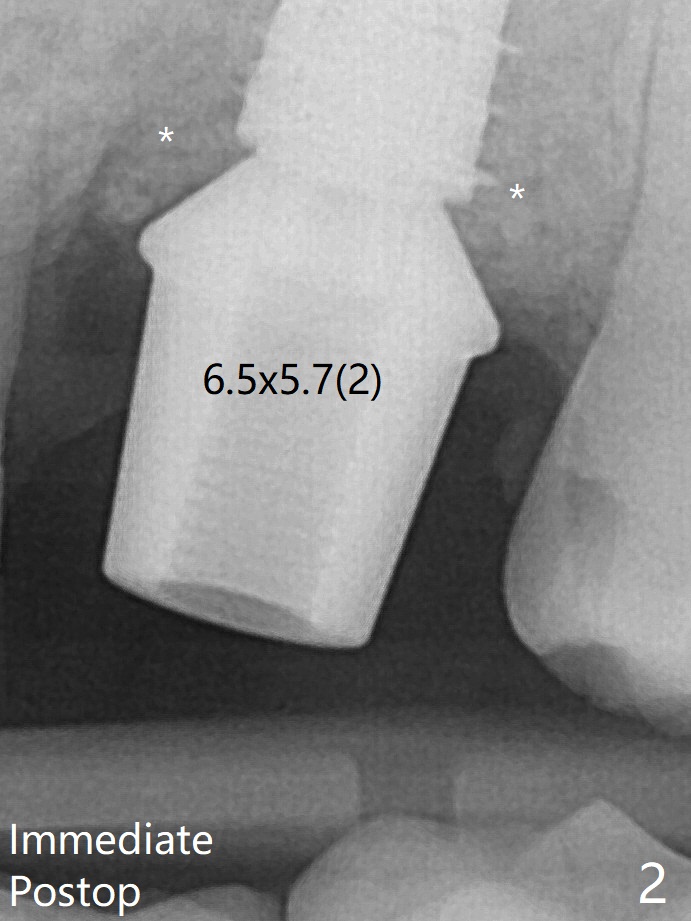

The bone graft is indistinguishable from the original alveolus 9 months postop (Fig.8 *).